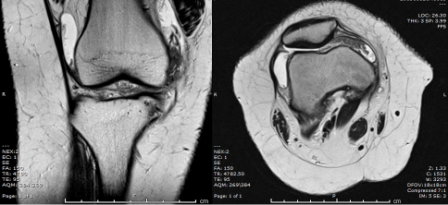

MRI of the knee was performed.

Q. What is your opinion on the MRI scan?

• Knee joint effusion

• Hypertrophy of the synovium

• Normal cartilage and bony outline. Meniscus, ACL, and PCL were intact.

MRI is the best approach showing the masslike synovial proliferation with lobulated margins, with low signal intensity and "blooming" artifact on gradient echo due to haemosiderin deposition [4].